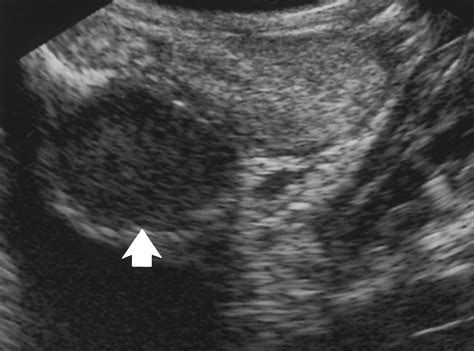

TitleSeminal Vesicle Cyst with Ipsilateral Renal Agenesis | AJR